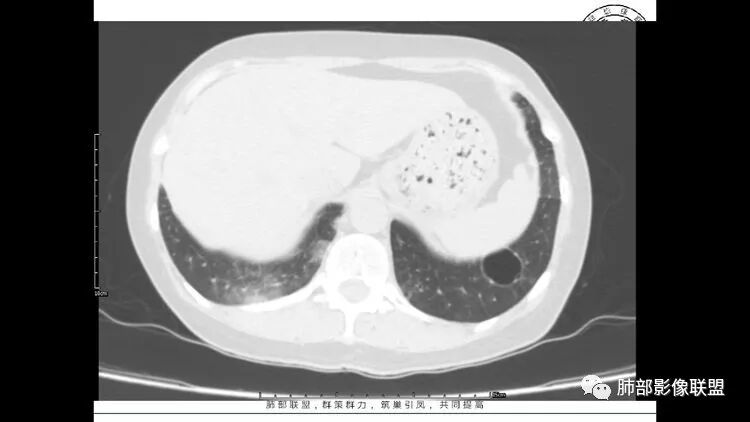

中年女性,因“角膜炎”入院,自用眼液2年,(眼干?)肺部:双肺多发类圆形薄壁气囊+实性结节+GGO,下肺分布为主,纵隔淋巴结肿大,考虑淋巴系统增殖,LIP可能性大,可能继发于干燥综合症;左肺下叶的混合磨玻璃结节形迹可疑,边界清晰,内部疑似空泡,扩张扭曲支气管,极像肺癌,伴双肺转移?待排吧

55岁女性,右眼红痛视力下降1天。既往有类风湿病史。两肺多发大小不等囊及结节,左下肺磨玻璃结节样病灶,纵隔占位。一元解释不了这么多不同病灶,二元甚至三元。纵隔恶性肿瘤并肺内转移?左下肺腺癌并肺内纵隔淋巴结转移?LIP?

多发气囊,气囊内可见血管进入,因患者眼干伴类风湿,可能有干燥综合征,那LIP可能性大。因为不是育龄期发病,可排除LAM。患者左纵膈淋巴结肿大,且有融合趋势,结合左下肺病灶,考虑合并恶性肿瘤,淋巴瘤?鉴别结节病

1.左下肺腺癌;2.两肺弥漫性病变(多发囊腔、部分囊壁不规则,分布无特异,结节,空洞,树芽征,GGO),结合眼部情况首先考虑LIP,不典型感染(病毒或其他)待排。

左肺下叶混杂密度病灶,其内可见空泡,周围ggo清楚,考虑浸润性腺癌。双肺散在多发薄壁囊腔和实性结节,以胸膜下及血管旁分布位于,气囊可见血管贴边征,双肺小叶间隔及中央间质增厚,局部可见磨玻璃影及树芽征,纵隔内淋巴结肿大,考虑LIP

综上,考虑左下肺浸润性腺癌+LIP

双肺多发大小不等囊腔,可见薄壁,部分囊腔内可见血管影,伴双肺多发结节,结合患者眼病及类风湿病史,考虑LIP可能大。另左肺下叶磨玻璃结节,边界清晰,内可见空泡,伴纵膈多发肿大淋巴结,不除外浸润性腺癌可能。

常规分析:右眼红疼1天,滴眼史两年,有类风湿病史,考虑有干燥综合征(SS)可能,需要了解自免抗体检测情况,双肺囊变需要考虑LIP,另右上叶前段GGO要鉴别腺癌或转移可能,右下叶背段多发树芽改变,双肺多发实性小结节,结核?左下肺混合性GGO考虑侵润性腺癌可能,双侧胸膜下多发结节,部分合并GGO改变,右侧腋窝及纵隔淋巴结多见,转移?最后问题来了,这个病人一元(腺癌合并转移,包括整个囊变,实性结节,胸膜下都是转移)?二元(LIP合并腺癌伴转移或者淀粉样变基础上的LIP)?三元(LIP+结核+腺癌伴转移)?

LIP影像重要线索一句话:

双肺下叶分布为主的间质改变(磨玻璃影、小叶间隔增厚)、散在气囊影(常有血管贴边)、边界不清小结节